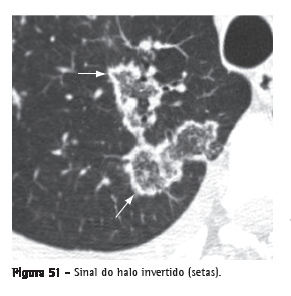

Sinal do halo invertido

Opacidade focal em vidro fosco circundada por um anel de consolidação completo ou parcial (Figura 51). Inicialmente descrito como um sinal de pneumonia em organização, já foi, entretanto, associado a outras doenças, tais como paracoccidioidomicose.(87,88)